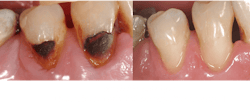

- GI or RMGI restorations for caries-active senior adults with continuing dental caries (figures 5 and 6)